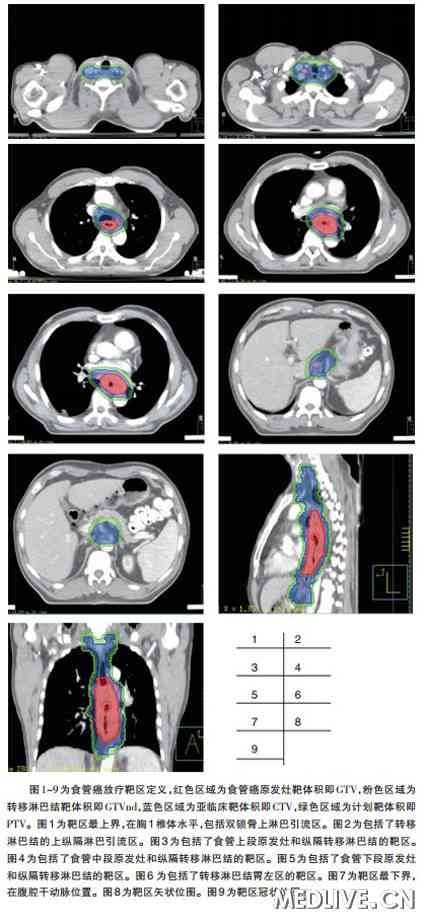

食管癌放疗靶区定义

图片尺寸426x922